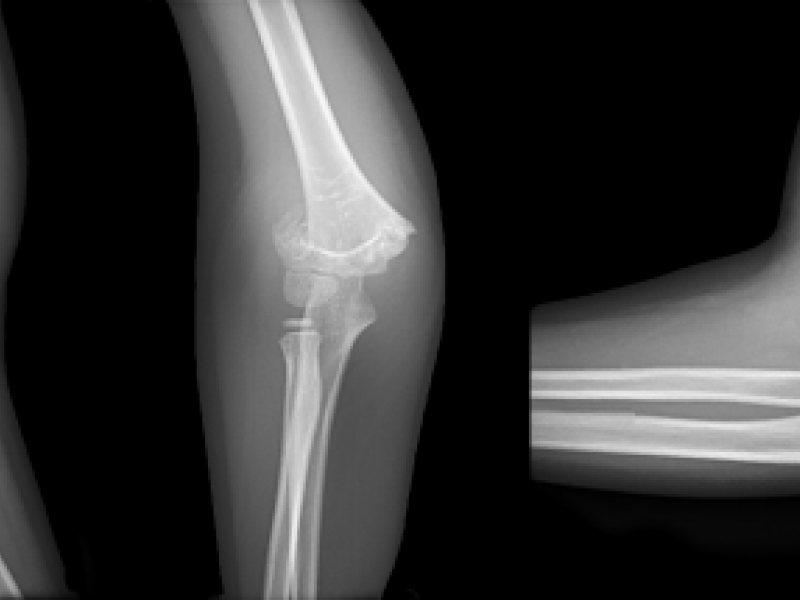

#EMconf: Finger injuries

June 15 2017